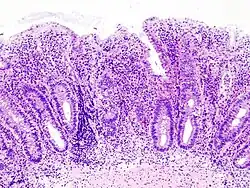

Histologic

Biopsies of the mucosa are taken during endoscopy to confirm the diagnosis of UC and differentiate it from Crohn's disease, which is managed differently clinically. Histologic findings in ulcerative colitis include: distortion of crypt architecture, crypt abscesses, and inflammatory cells in the mucosa (lymphocytes, plasma cells, and granulocytes).[28] Unlike the transmural inflammation seen in Crohn's disease, the inflammation of ulcerative colitis is limited to the mucosa.[28]